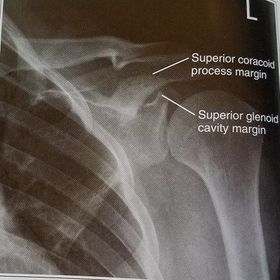

| Posterior Oblique Grashey | ANATOMY: glenoid cavity in profile glenohumeral joint center of VOI CRITERIA: open glenoid cavity anterior/posterior rims of glenoid cavity are superimposed POSITIONING: pt in 35-40 degree posterior oblique CR perpendicular @ glenoid cavity |